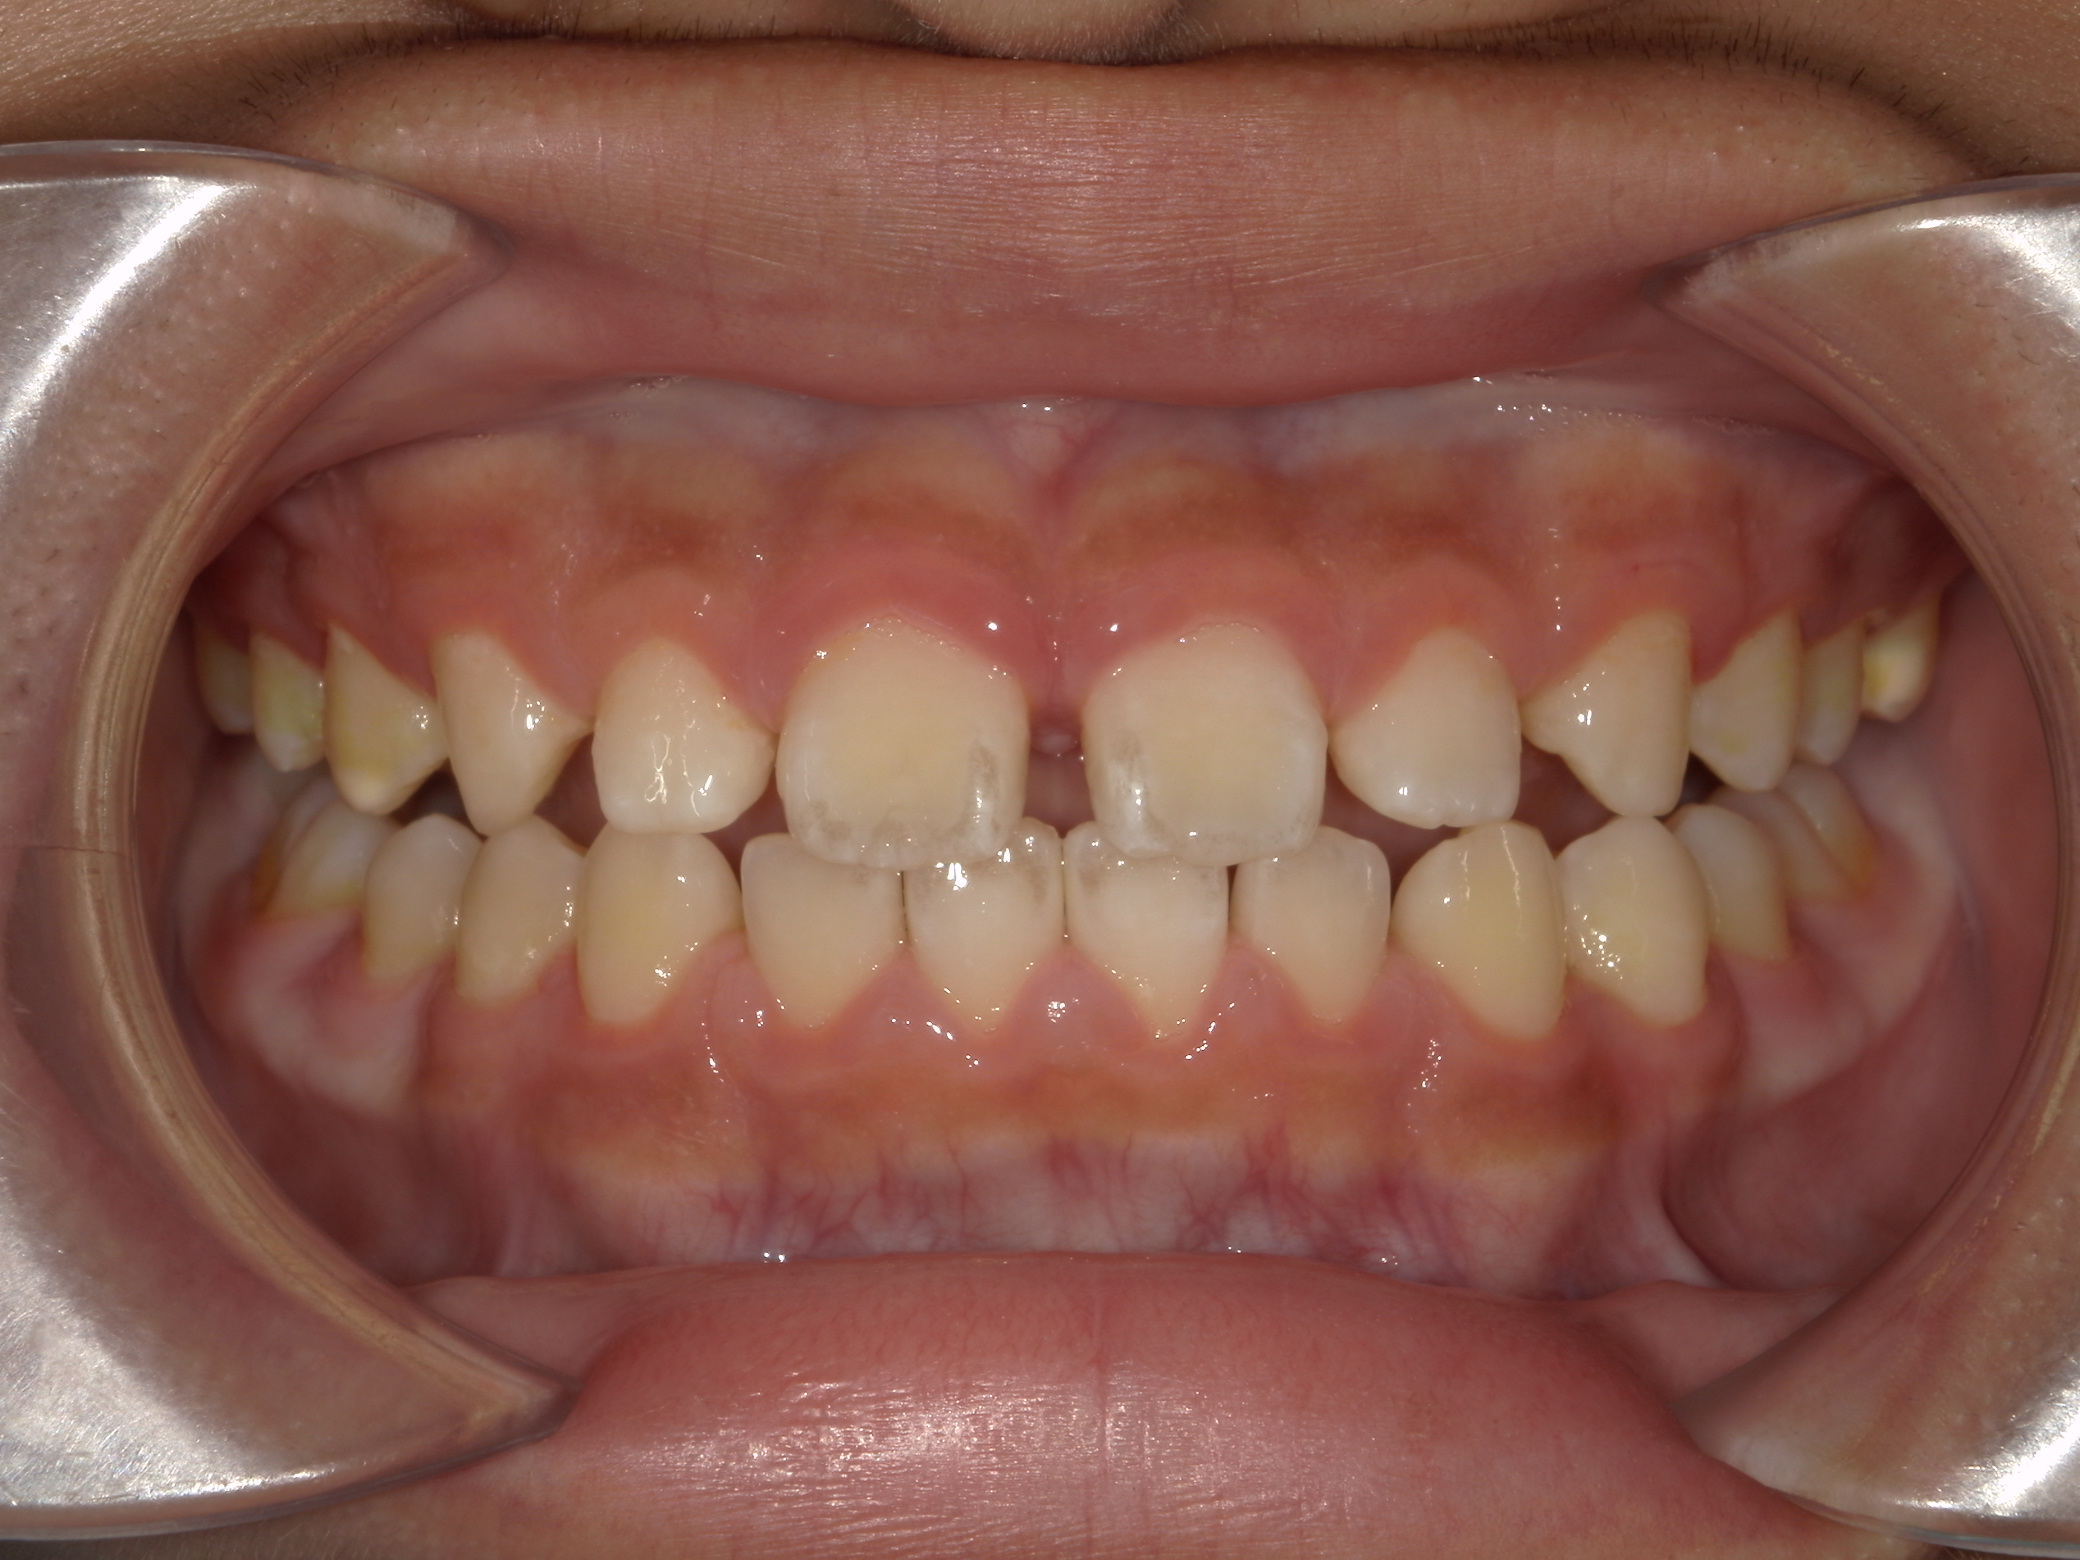

受け口(上顎歯列弓狭窄による臼歯部交叉咬合)

6歳 男性

治療例前

治療例後

治療法

上顎歯列拡大による交叉咬合の改善

装置

急速拡大装置

使用装置写真

費用

495,000円(税込)

期間

約1年半

付記

上顎がかなり狭窄した状態でした。固定式拡大装置で歯列および顎骨を拡大し、奥歯のかみ合わせも改善しています。

中学生以降になると骨が固くなりこのようにキレイには拡大できないため早期治療が功を奏した例です。

2期治療のための精密検査が必要です。

リスク:歯肉退縮、歯根吸収、後戻り、予期せぬ成長